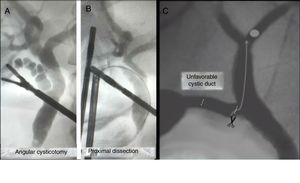

New dissection of the cystic ductAdequate dissection of the cystic duct provides a critical view of safety. However, in unfavorable cystic ducts (twisted or presenting cystic duct stones7,8), it is difficult to perform intraoperative cholangiography, and even more so transcystic instrumentation.

In these cases, a new dissection of the duct closest to the main bile duct is necessary, allowing us to straighten the pathway and perform a new cysticotomy while facilitating canalization and subsequent instrumentation (Fig. 4A and B).

Angular cysticotomy or minimal choledochotomyThe presence of intrahepatic stones is uncommon, and even more so is the impossibility of descending them beyond the cystic-choledochal junction. When faced with this exceptional situation, we perform a new cysticotomy on the lower side, close to the junction, which allows us to direct the basket snare towards the intrahepatic bile duct.9

In some cases, closure must be performed with stitches due to the proximity with the main bile duct (Fig. 4C).